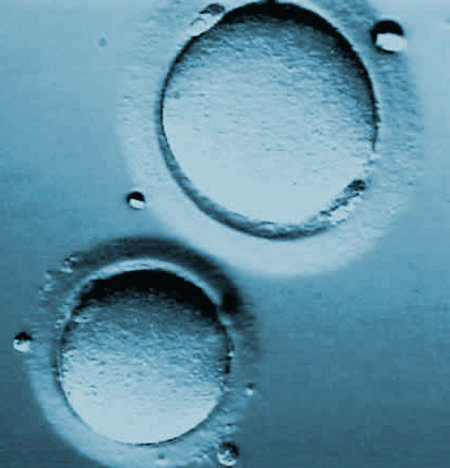

La donante es sometida a un tratamiento hormonal de estimulación ovárica con el fin de lograr que en el momento de la donación se ovulen varios ovocitos, pues no todos reunirán las condiciones necesarias para ser fecundados. Los óvulos se obtienen mediante aspiración guiada por ecografía.